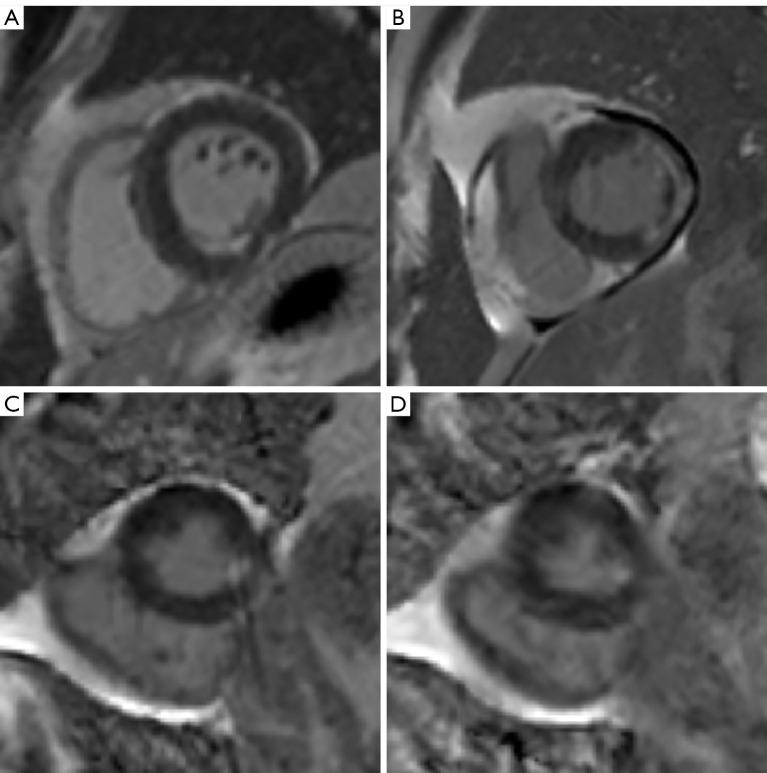

Segmented phase-sensitive inversion recovery (PSIR) turbo fast low-angle shot (FLASH) has become the reference standard sequence for late gadolinium enhancement (LGE) cardiac magnetic resonance (CMR) imaging. However, it has a long scanning time, requires multiple breath holds, and is prone to motion artifacts. This study aimed to compare the accuracy of two fast LGE sequences with FLASH PSIR in acute myocardial infarction (AMI) detection and quantification of LGE.

A total of 110 AMI patients (90 males, 58.61±10.9 years) were included in our analyses. Of these, 100 patients (84 males, 58.6±10.9 years) presented LGE (+), and 60 patients developed MVO. Participants were divided into three groups according to the LGE results, namely LGE (-), LGE (+) without MVO, and LGE (+) with MVO. The overall IQ score and CNR for the two fast sequences [single-shot true fast imaging with steady-state precession (TrueFISP PSIR), PSIR motion-corrected, free-breathing single-shot balanced steady-state free precession (moco bSSFP)] were significantly higher than those for the FLASH PSIR (P<0.001). On visual assessment, the number of layers (P=0.20 and 0.22, respectively) and segments (P=0.09 and 0.32, respectively) for LGE displayed no difference and showed excellent matching with those of FLASH PSIR. There were no significant differences in LGE mass (P=0.61 and 0.83, respectively) and MVO mass (P=0.15 and 0.55, respectively) between the FLASH PSIR and the two fast sequences.

分段相敏反转恢复(PSIR)快速低角度激发(FLASH)已成为延迟钆增强(LGE)心脏磁共振(CMR)成像的参考标准序列。然而,其扫描时间长,需要多次屏气,且容易出现运动伪影。本研究旨在比较两种快速LGE序列与FLASH PSIR在急性心肌梗死(AMI)检测及LGE定量方面的准确性。

共有110例AMI患者(90例男性,年龄58.61±10.9岁)纳入分析。其中,100例患者(84例男性,年龄58.6±10.9岁)出现LGE(+),60例患者发生MVO。根据LGE结果将参与者分为三组,即LGE(-)组、无MVO的LGE(+)组和有MVO的LGE(+)组。两种快速序列[单次激发稳态进动真快速成像(TrueFISP PSIR)、PSIR运动校正自由呼吸单次激发平衡稳态自由进动(moco bSSFP)]的整体IQ评分和CNR均显著高于FLASH PSIR(P<0.001)。视觉评估显示,LGE的层数(分别为P=0.20和0.22)和节段数(分别为P=0.09和0.32)无差异,且与FLASH PSIR的层数和节段数匹配良好。FLASH PSIR与两种快速序列在LGE质量(分别为P=0.61和0.83)和MVO质量(分别为P=0.15和0.55)方面无显著差异。